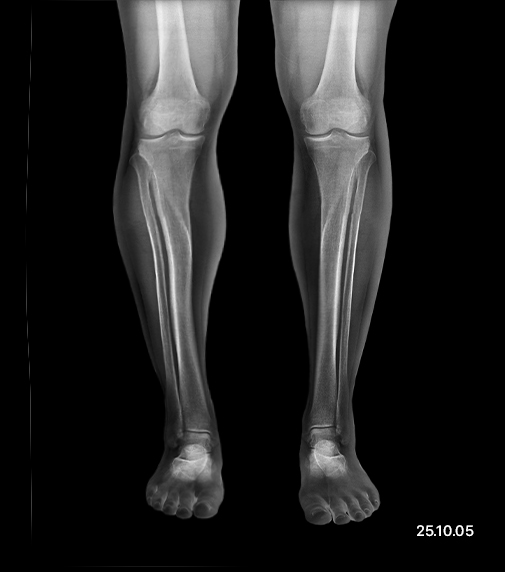

Before and After

- Before

- After